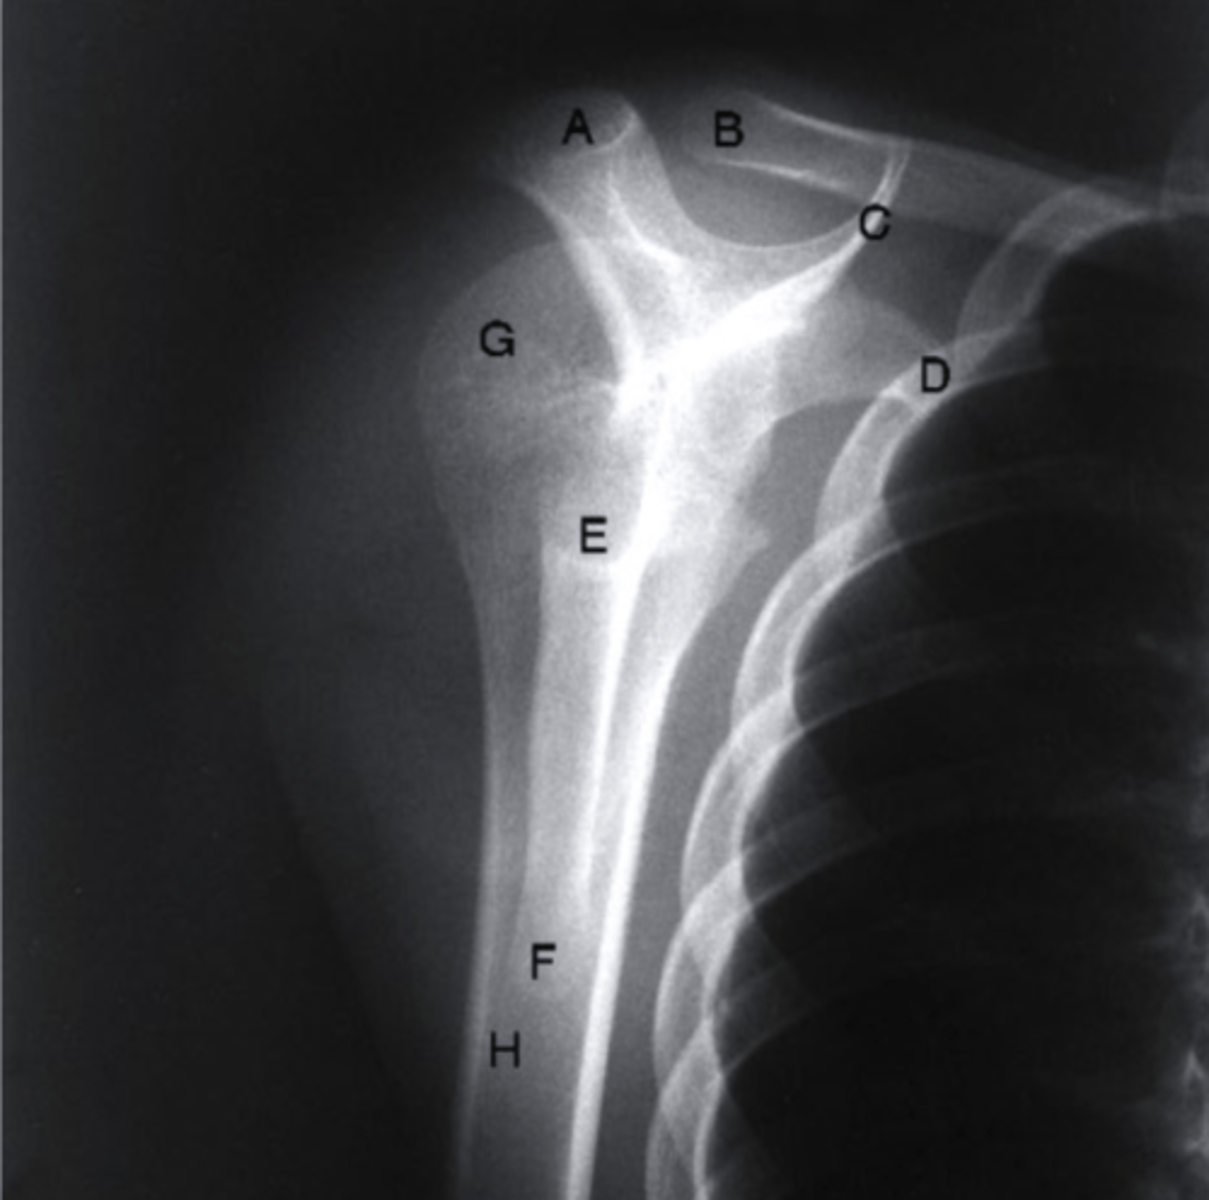

AP + ER

What view is this?

clavicle

what does the pink line point to?

spine of scapula

coracoid process

AC joint

acromion

Humeral Head

Greater Tuberosity

lesser tuberosity

Anatomic Neck of Humerus

Surgical Neck of Humerus

Shaft of Humerus

glenoid fossa

body of scapula

axillary border of scapula

vertebral border of the scapula